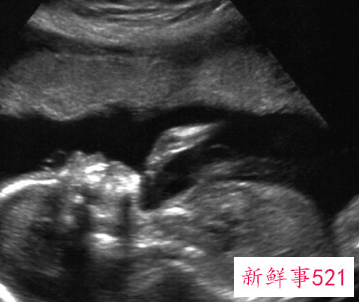

第二次b超检查的时间,应该在怀孕第24周左右进行。这一次的b超检查,主要是为了排畸。这个时候胎儿基本所有器官都已长成,b超重在筛是否存在先天性畸形。

第二次B超检查一般安排在妊娠中期(怀孕20周左右),此时宫内羊水相对较多,胎儿大小比较适中,宫内有较大的活动空间,对B超检查来说,有较好的对比度,可以清晰地看到胎儿各个器官。较明显的畸形,如先天性心脏病,无脑儿,脑积水,脊柱裂,腹壁缺损,四肢短小,多囊肾,消化道闭锁等容易被发现。如果有必要,可以及时进行治疗或终止妊娠。